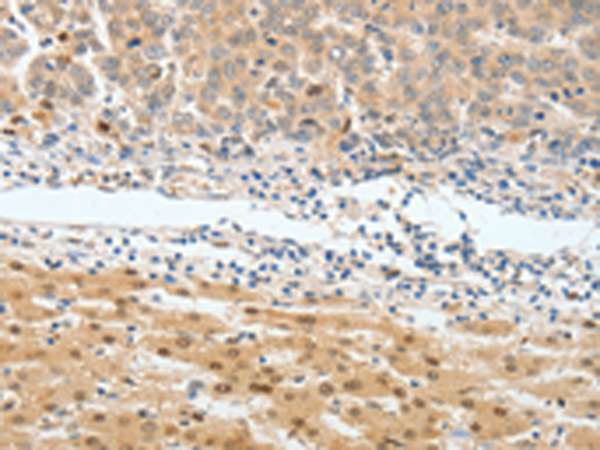

分类: 科研抗体货号: P11002别名: RYSR, BPIL1, LPLUNC2, C20orf184, dJ726C3.2应用: IHC反应种属: Human, Mouse